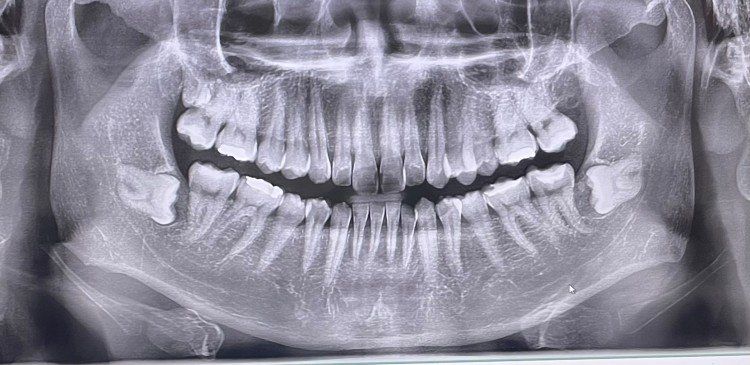

+사랑니 엑스레이 사진도 첨부하겠습니다. 치과에서는 빼지 말라고 위험해보인다고만 말하고 두통은 계속있고.. 미치겟네요

• 1번 째 사진

• 2번 째 사진